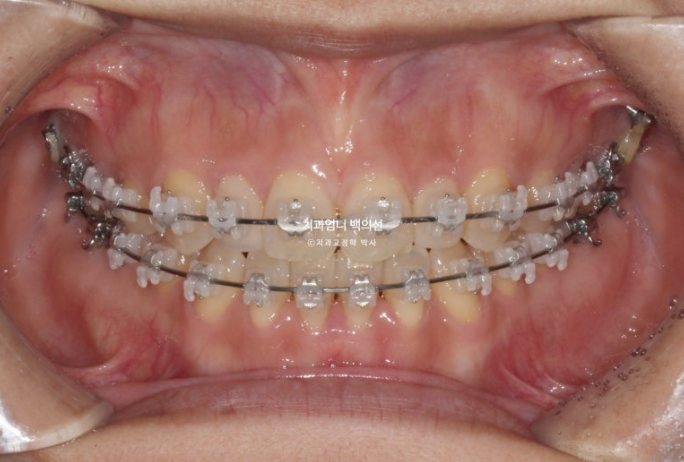

23.05

2년전 앞니 개방교합 치료를 위해 내원한 30대 환자분입니다.

앞니 벌어진 양이 5mm라 양악수술과의 경계지만 양악수술생각은 없으셔서 교정만으로 해결하기로 했습니다.

앞니 약간 삐뚠 부분도 함께 해결하기로 하고 치료에 들어갑니다. 클리피씨 교정을 권유드렸습니다.